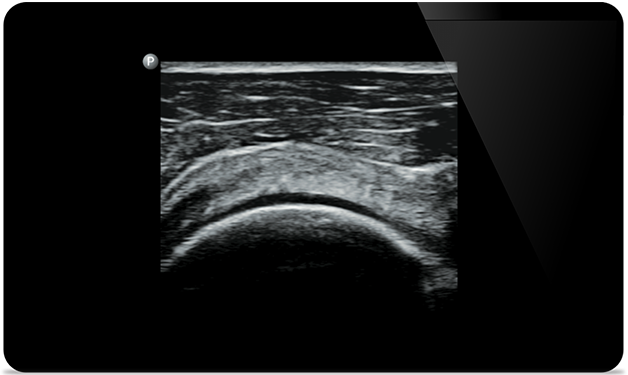

Lumify helps you see the fine details in muscles, joints, ligaments, tendons and cartilage to make a more accurate diagnosis of injuries.

Lumify can help you assess patients from head to toe, whether it’s plantar fasciitis, tendonitis or bursitis in the patellar tendon, or even shoulder instability in the rotator cuff.

Supraspinatus tendon tear